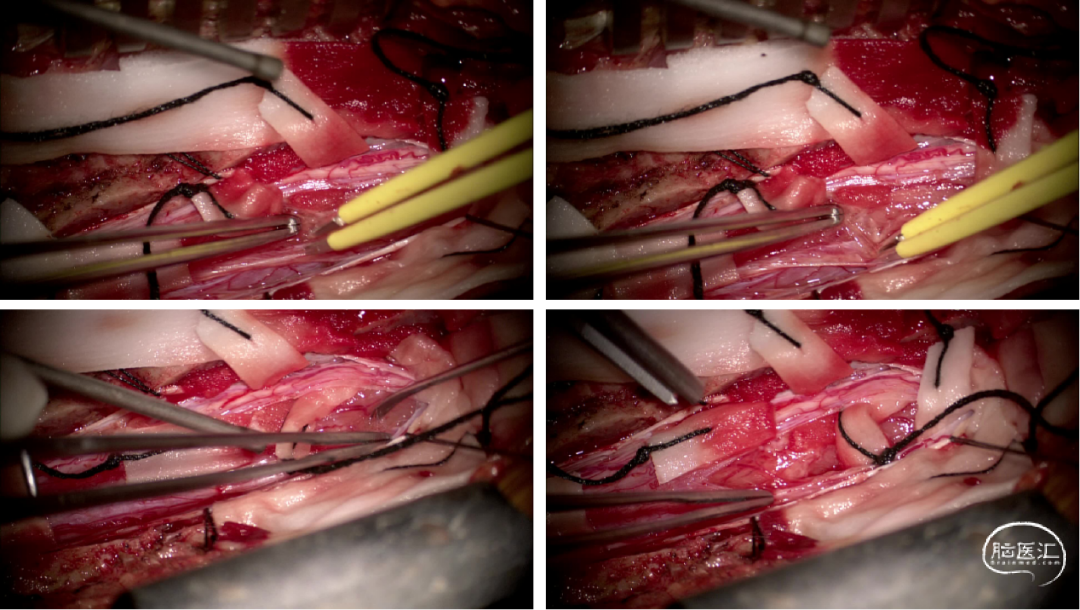

手术情况

硬脊膜张力高,脊髓向背侧膨出,与脊髓腹侧粘连紧密,肿瘤挤压脊髓,肿瘤边界分离,减少对胸髓的牵拉,降低了术后患者神经功能发生的概率,术后患者肢体麻木症状改善。